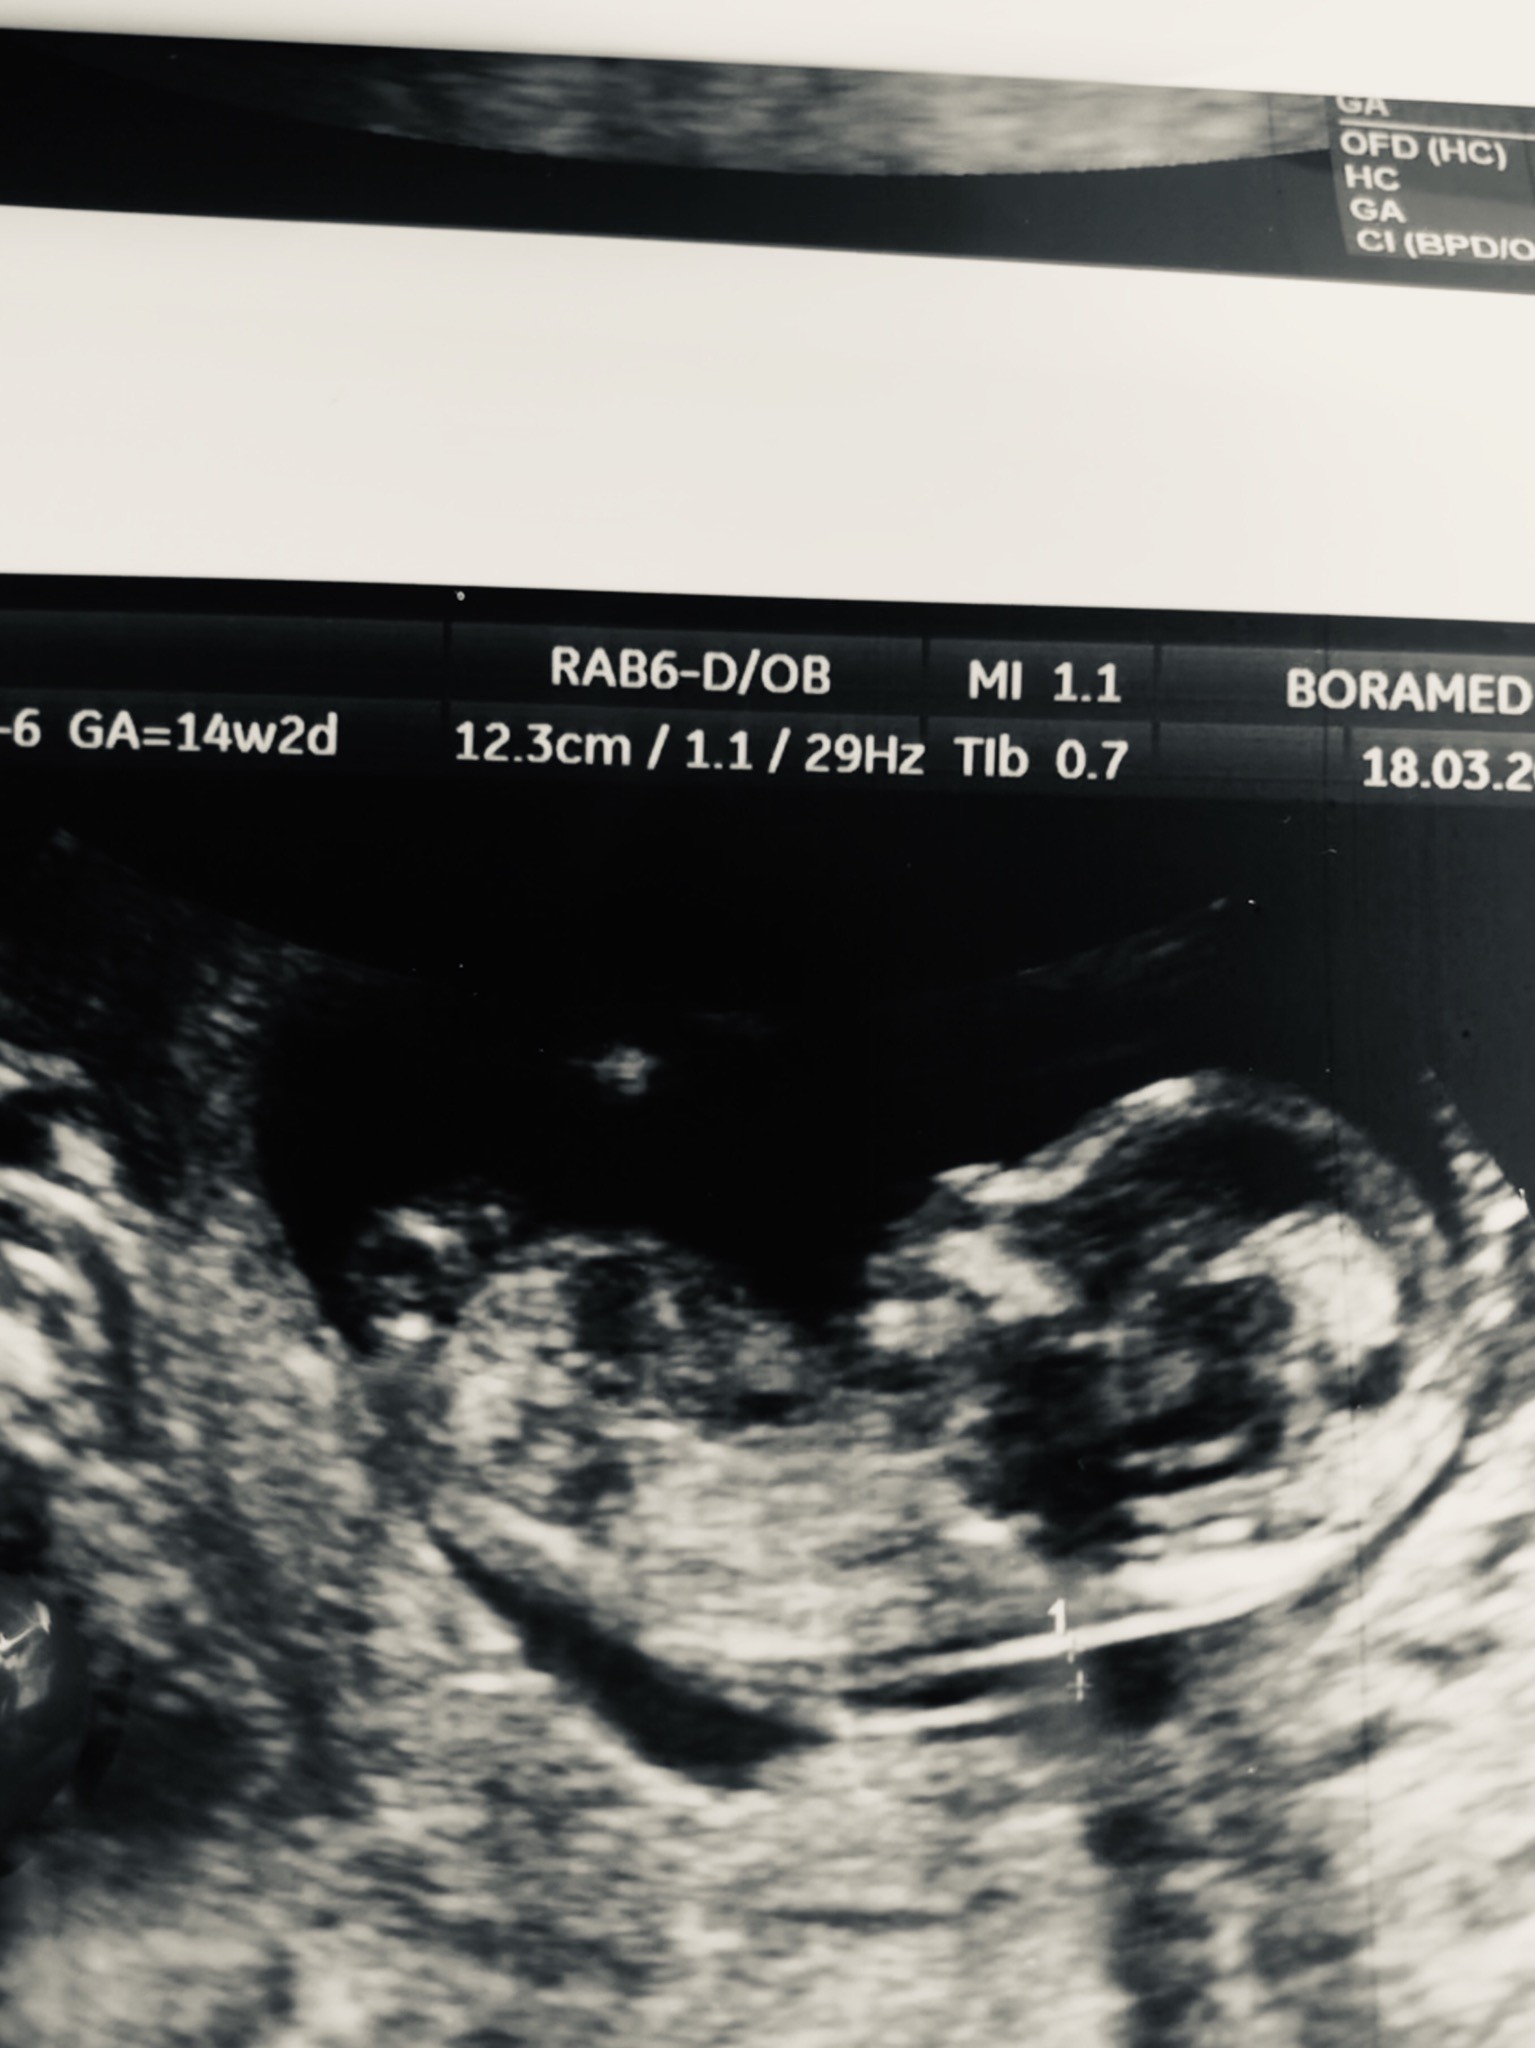

Usg chłopak czy dziewczynka

Witam w 19 tygodniu ciąży dowiedziałam się ze będę miała dziewczynkę w 20 tyg okazało się jednak , że to chłopak. Sama już nie wiem bo na jednym usg widać na pewno dziewuche a na drugim chłopca. Może to pempowina ?? Może ktoś mi pomoże rozwiązać ta zagadkę

Załączniki

• 4A8F5FF1-76CA-4DE0-AC12-5EDF08E820F2.jpg

4A8F5FF1-76CA-4DE0-AC12-5EDF08E820F2.jpg

596,4 KB · Wyświetleń: 44 156